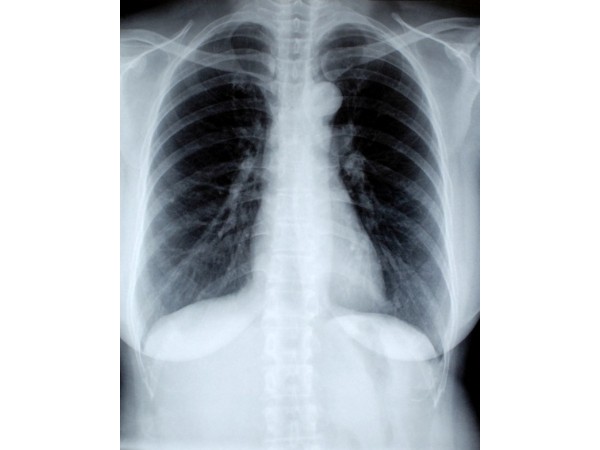

Mammography involves the compression of the mammary gland between two plates and an X-ray is transmitted through the breast tissue [12]. Mammography helps to detect the development of breast cancer in women who have no signs or symptoms of the disease, as well as any lump or other signs of breast cancer [13]. All women should have a mammography to screen for breast cancer and women over age 75, there is no recommendation [14].